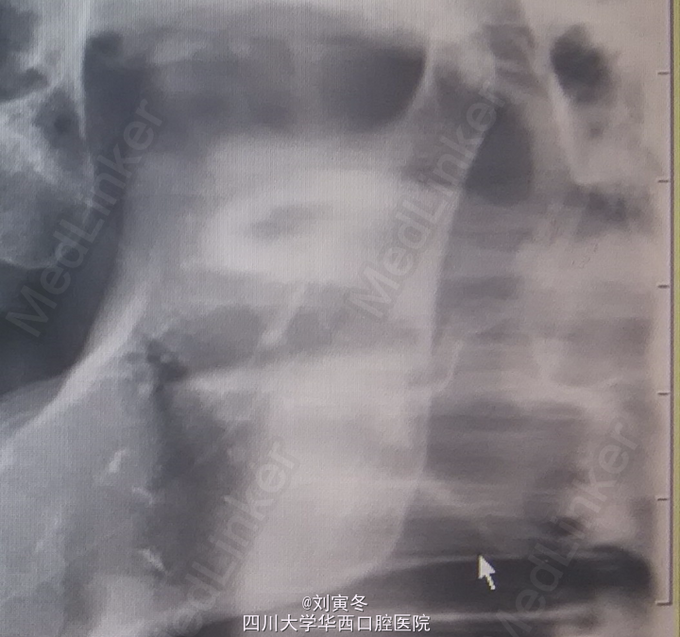

患者女,46岁 主诉:双侧咽部不适3+月 现病史:3+月前自觉双侧咽部不适,病情反复,要求治疗 既往史:既往体健,无颈椎病相关症状

检查: 未扪及双侧颈部淋巴结肿大,双侧关节检查无明显阳性体征 口内未见明显包块病变,咬合关系良好 咽侧壁触诊可引出不适 全景片: 右侧茎突长度约3cm,左侧茎突形态异常,长度约4cm

诊断:茎突综合征 处置:建议观察,如出现不适复诊治疗

茎突综合征又称为Eagle综合征,常见于成年人,单侧患病多见。临床表现多种多样无特异性,诊断有一定的困难。 茎突由第二鳃弓发育而来,附着有茎突舌骨韧带,茎突舌肌,咽上缩肌等口咽部肌肉。如出现茎突长度过长,方向和形态改变,均可引起咽部的疼痛不适,异物感,阻塞感等异常感觉。由于吞咽或运动时异位的茎突会刺激周围组织,导致症状加重。疼痛可放散至耳部或头部 目前,茎突长度大于3cm可认为其长度过长,冠状位上茎突与中线的角度大于40度或小于20度均可认为茎突方向异常。主要采用X线和CT检查 该病的治疗主要是保守与手术治疗。手术治疗适用于自觉症状重者,可经口咽或颈外入路切短茎突。